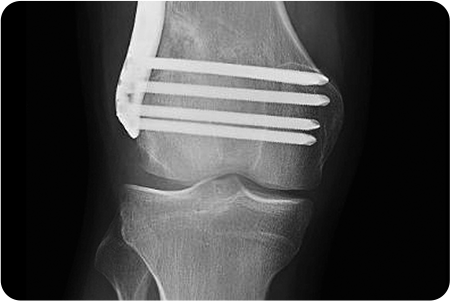

1

무게 중심이 내측으로

쏠려 있는 O다리 수술

경골을 절골하여 원하는 각도로 벌려 무게 중심이

바깥쪽으로 옮겨지도록 교정

합니다. 절골한 부위를

금속판과 나사로 고정해 뼈가 안정적으로 붙도록 합니다.